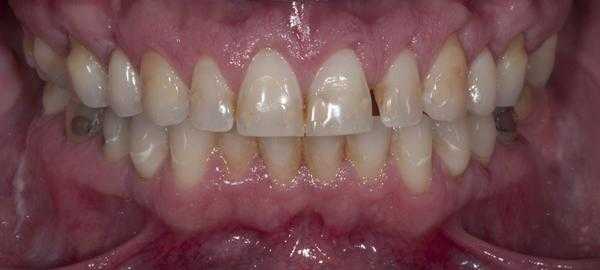

Представленный ниже клинический случай демонстрирует, как vonlays могут быть использованы в качестве альтернативы полным коронкам для восстановления поврежденных задних зубов.

Клинический случай

Пациент обратился за помощью с несколькими основными жалобами, главной из которых являлась эстетическая дилемма: ему не нравился цвет, размер и форма зубов (фото 1). При этом он также желал по возможности закрыть диастему между 10 и 11 зубами. Он также был обеспокоен «объемом» собственной улыбки и хотел расширить форму зубной дуги так, чтобы улыбка казалась более полной. Во время стоматологического осмотра было установлено, что пациент имел умеренную степень стирания режущих и окклюзионных поверхностей, легкую генерализированную форму рецессии с локализированной умеренной рецессией в области первых моляров верхней челюсти. Большинство боковых зубов имели амальгамные реставрации небольших и средних размеров с признаками вторичного кариеса. На 18 и 29 присутствовали металлокерамические конструкции. Все передние зубы верхней челюсти и несколько передних зубов нижней челюсти имели композитные пломбы в интерпроксимальных зонах, которые со временем изменили свой цвет.

Фото 1. Вид зубов пациента перед вмешательством.